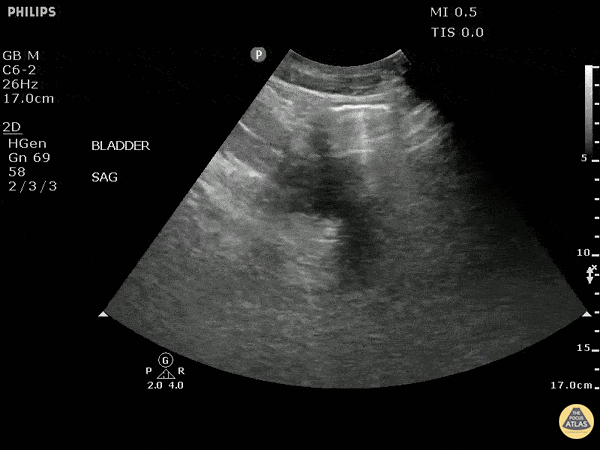

This sagittal image of the bladder demonstrates air within the bladder. This could be from emphysematous cystitis but could also be iatrogenic due to recent foley placement. Also note the presence of layered echoes in the bladder due to an infectious process. Image courtesy of Robert Jones DO, FACEP @RJonesSonoEM Director, Emergency Ultrasound; MetroHealth Medical Center; Professor, Case Western Reserve Medical School, Cleveland, OH View his original post here